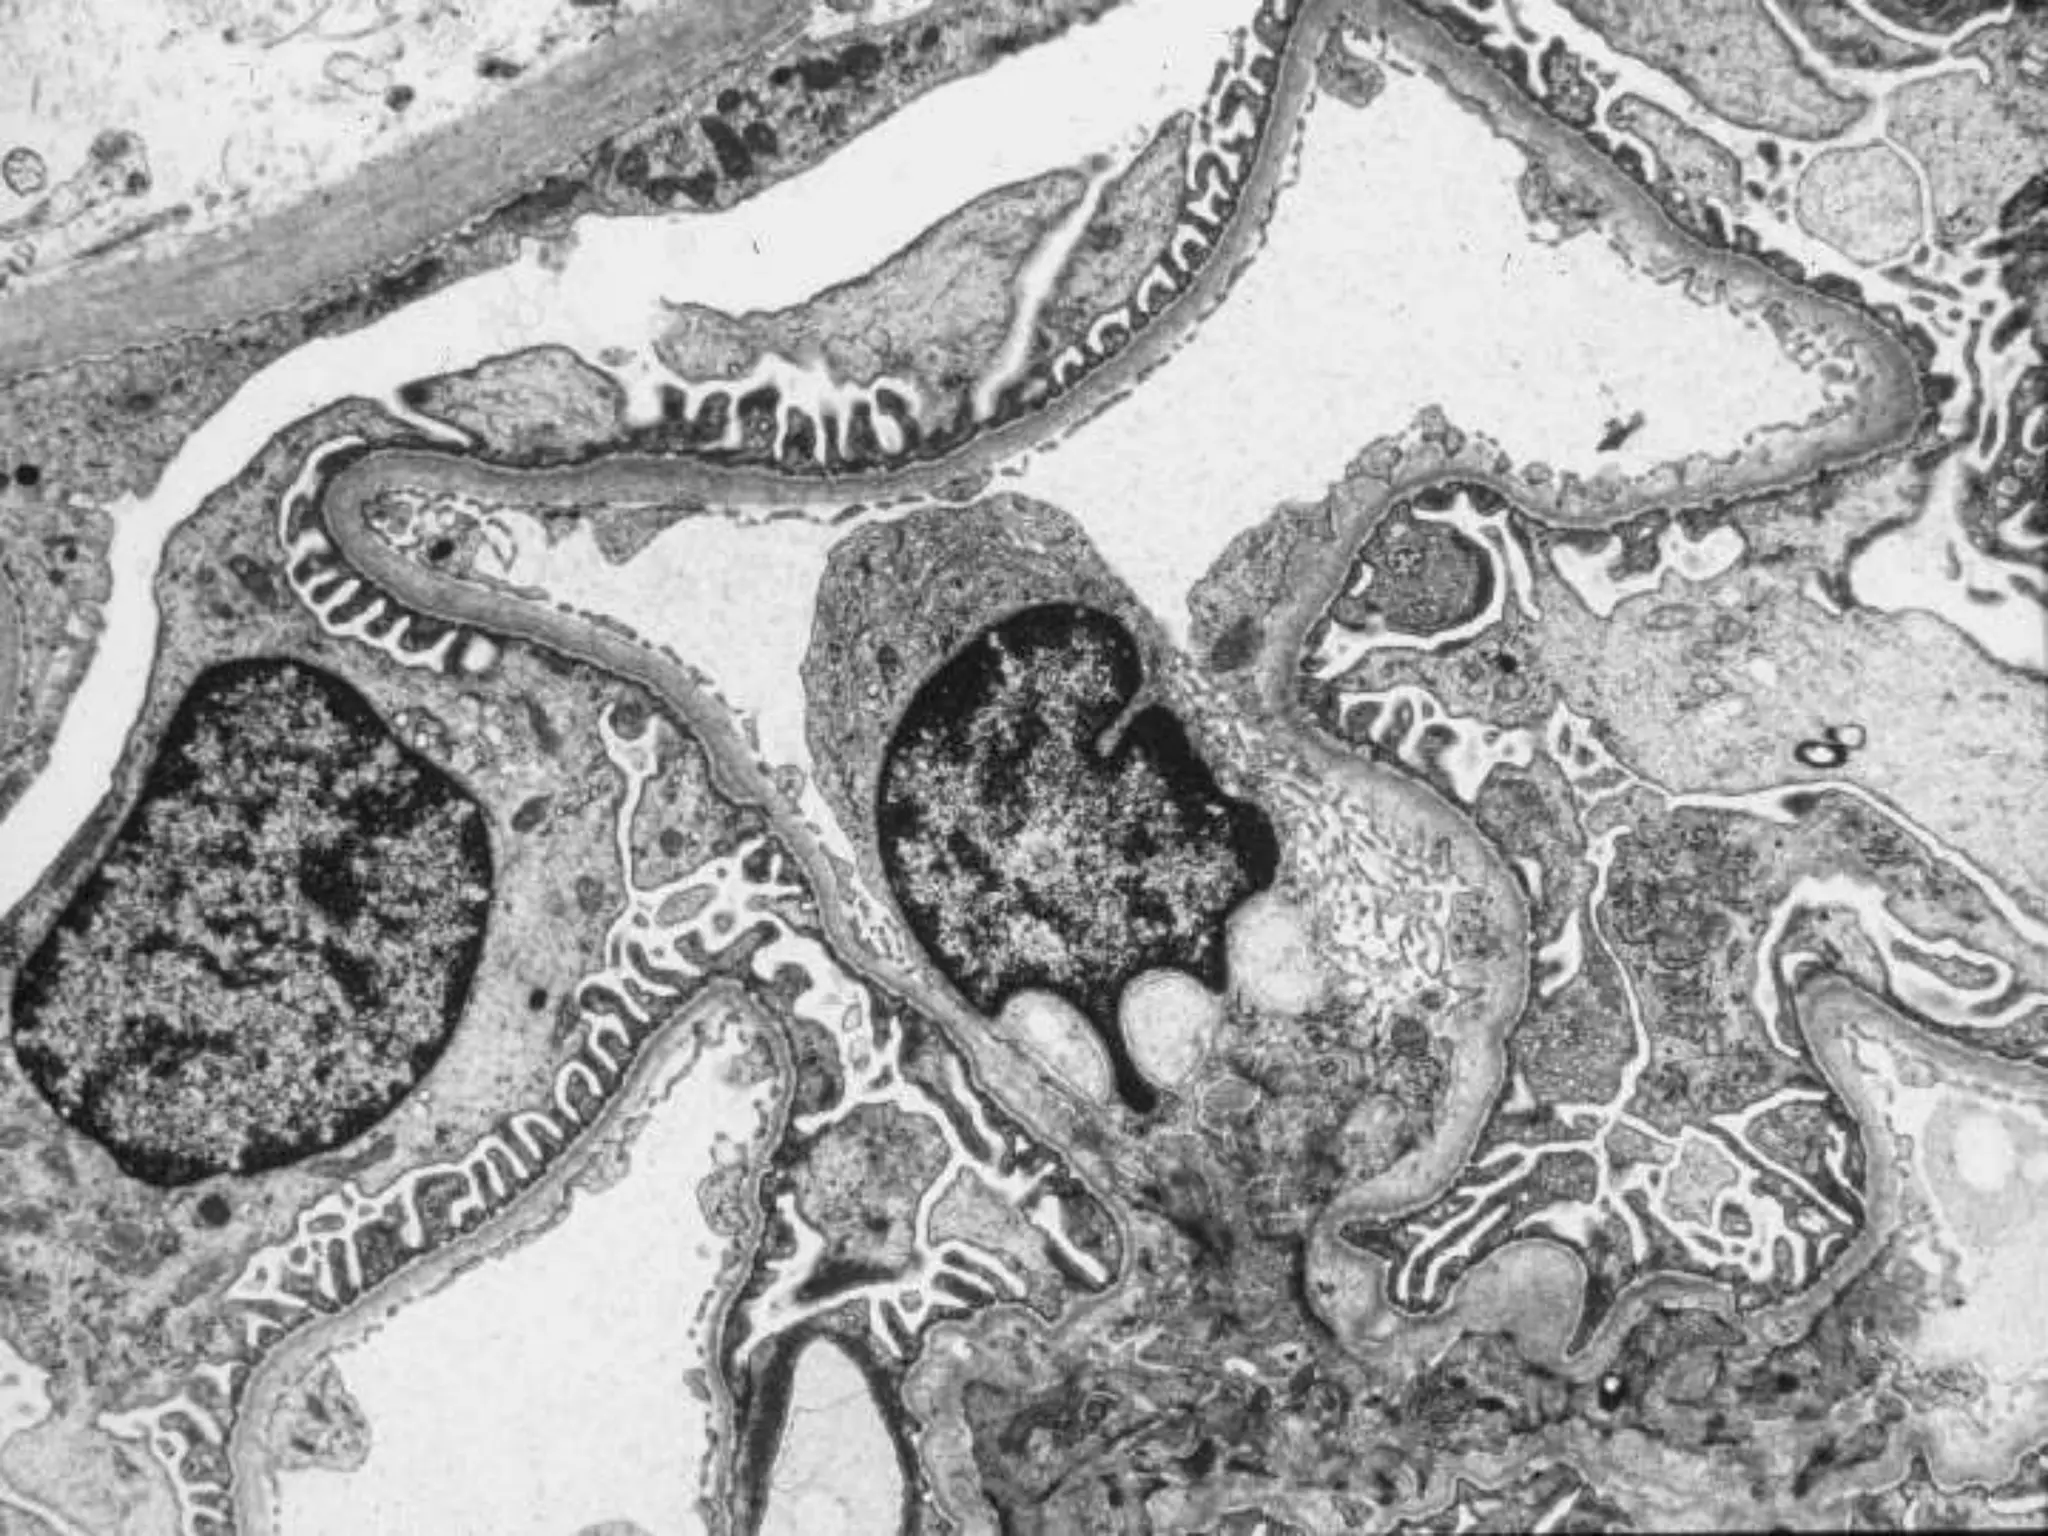

This document discusses recent treatments for lupus nephritis and summarizes a case study. It reviews definitions of glomerular pathology, the pathogenesis of lupus nephritis including the role of immune complexes, and the WHO classification system. It summarizes recent clinical trials comparing cyclophosphamide and mycophenolate mofetil as induction therapies, and azathioprine versus mycophenolate mofetil for maintenance. Rituximab was not found to be superior to placebo as an add-on therapy in one trial. The document recommends treatment and reviews considerations for a specific unemployed African American male patient with new onset nepus nephritis.